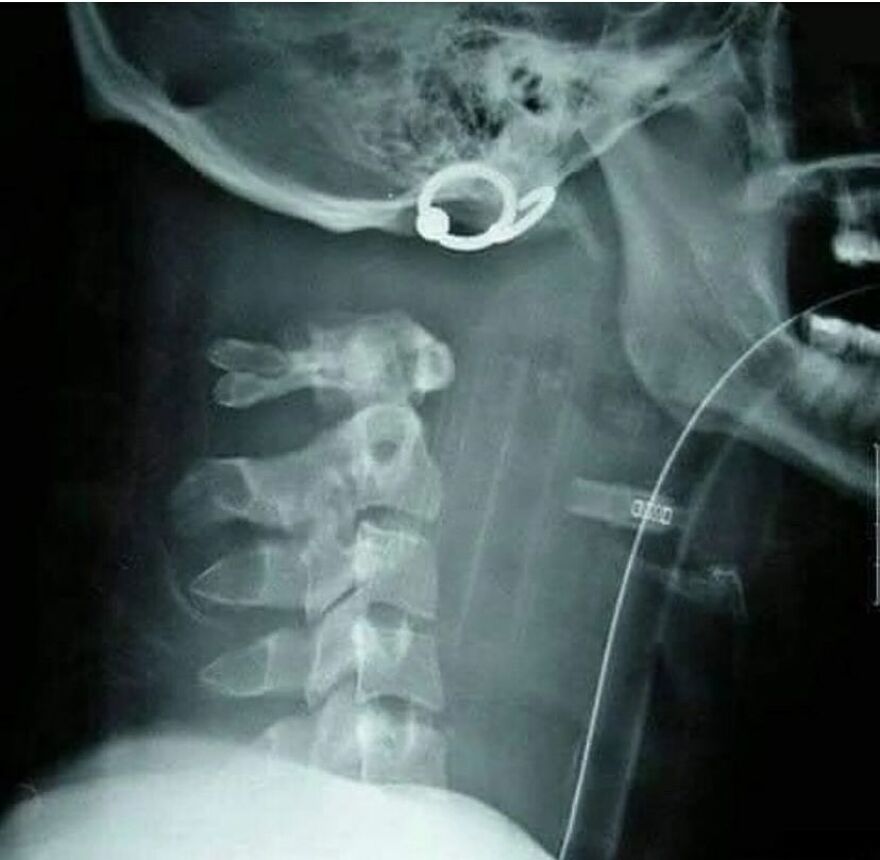

Vnútorná dekapitácia